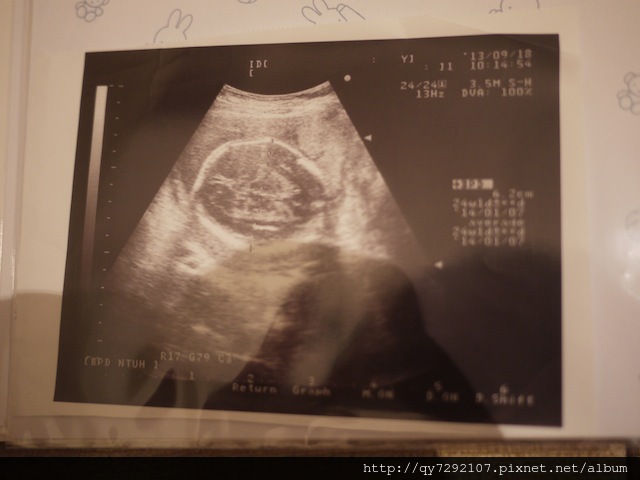

2013/07/23~胎盤過低

這是出血2之後,第一次回診,內心實在有點緊張,出血已經完全停止,子宮還是有點緊,Pony一切良好,只是醫生說:你的胎盤位置有點低,距離子宮頸口只有4公分,所以容易出血,現在開始,不要常走路,不可以提重物,不可以太勞累,不可以久站,多躺多休息,安胎藥繼續吃,等到胎兒越來越大,胎盤很可能就會隨著子宮變大而往上拉,所以先不用太擔心,今天開始~我要當茶來伸手飯來張口的貴婦!(這位太太,你當貴婦,那是誰要照顧妹醬,誰要煮三餐?!嗚~~~)

2013/07/30~胎盤上升

今天是出血2過後的第二次回診,已經2週都沒出血,但還是不太能走,走一小段路肚子就緊緊的宮縮,不過今天回診之後,醫生說隨著子宮變大,Pony的成長,胎盤已經逐漸往上升高,可以不用再吃藥了,YA!我的Pony真是好孩子,前晚我要跟他/她說要趕快長大,幫媽媽把胎盤拉高,就不會再宮縮出血了,今天檢查,胎盤就真的拉高了,胎盤一拉高之後,走路就不在有下墜感,腹部也不再緊縮了,又可以當回一個靈活的孕婦,我真是太開心了,Thank you , my dear Pony!現在就等著8/2跟姐姐一起帶著妹醬回台灣過夏天兼養胎了!